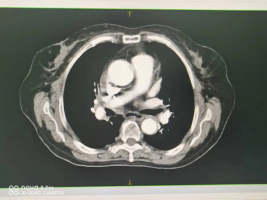

(四)肺癌

行IMRT治疗半程CT图像对比图